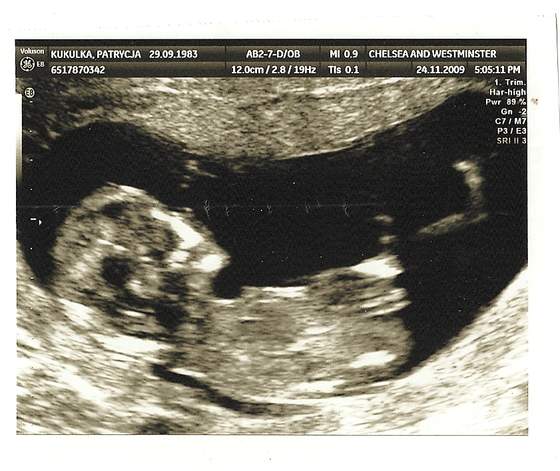

witajcie jestem majowka 2010:-) ogladam sobie wasze zdjecia z USG i moge powiedziec na 100% ze bedziesz miala coreczkepatrzac na twoje USG